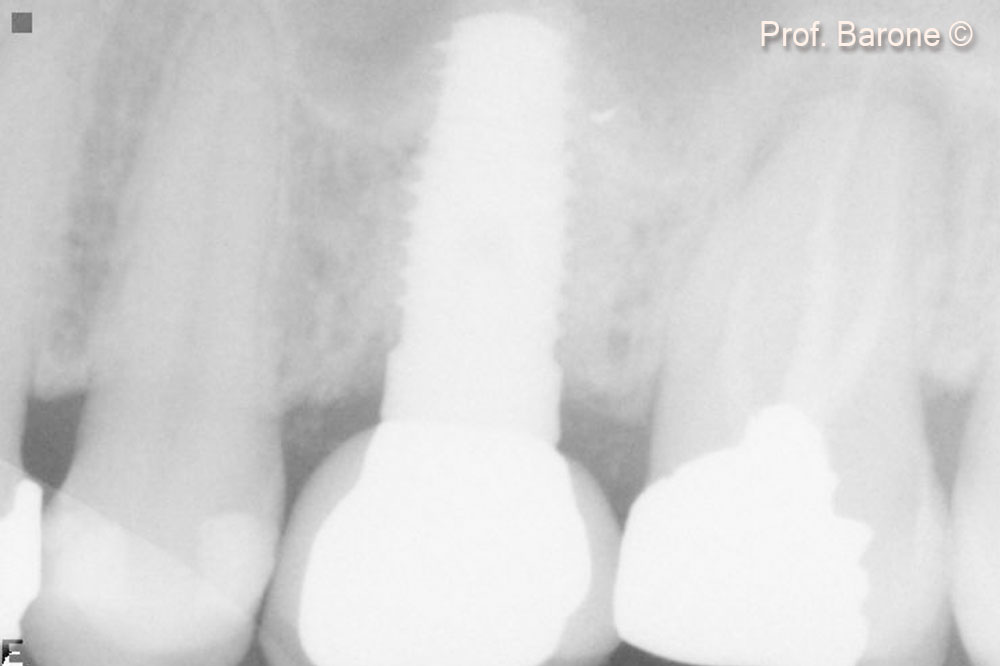

Hình ảnh X-quang quanh chóp răng sau 3 năm theo dõi.